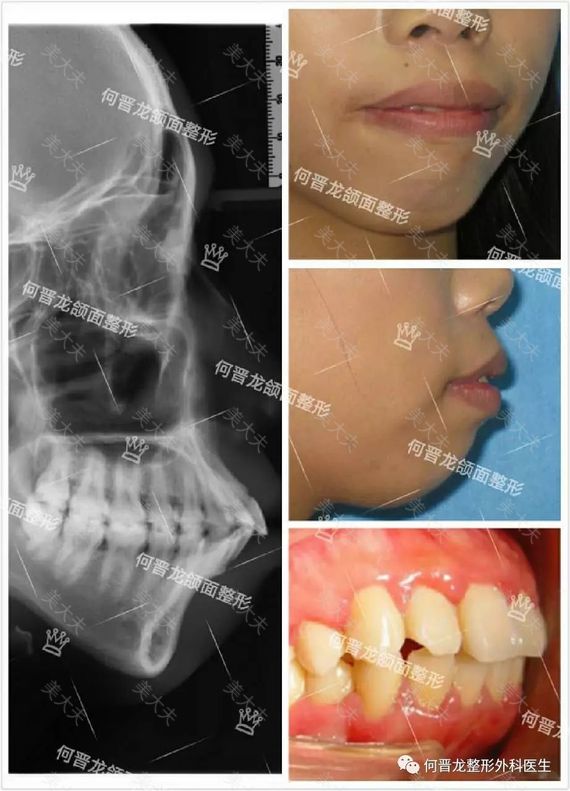

(一)、患者,24岁,在校学生

诊断:双颌前突,颏部发育不足

头影测量:SNA100°,SNB92°,NA7mm,NB1mm。

手术:上颌前部截骨术及下颌前部根尖下截骨术

设计:上颌后退5mm,下旋2mm;下颌后退4mm。